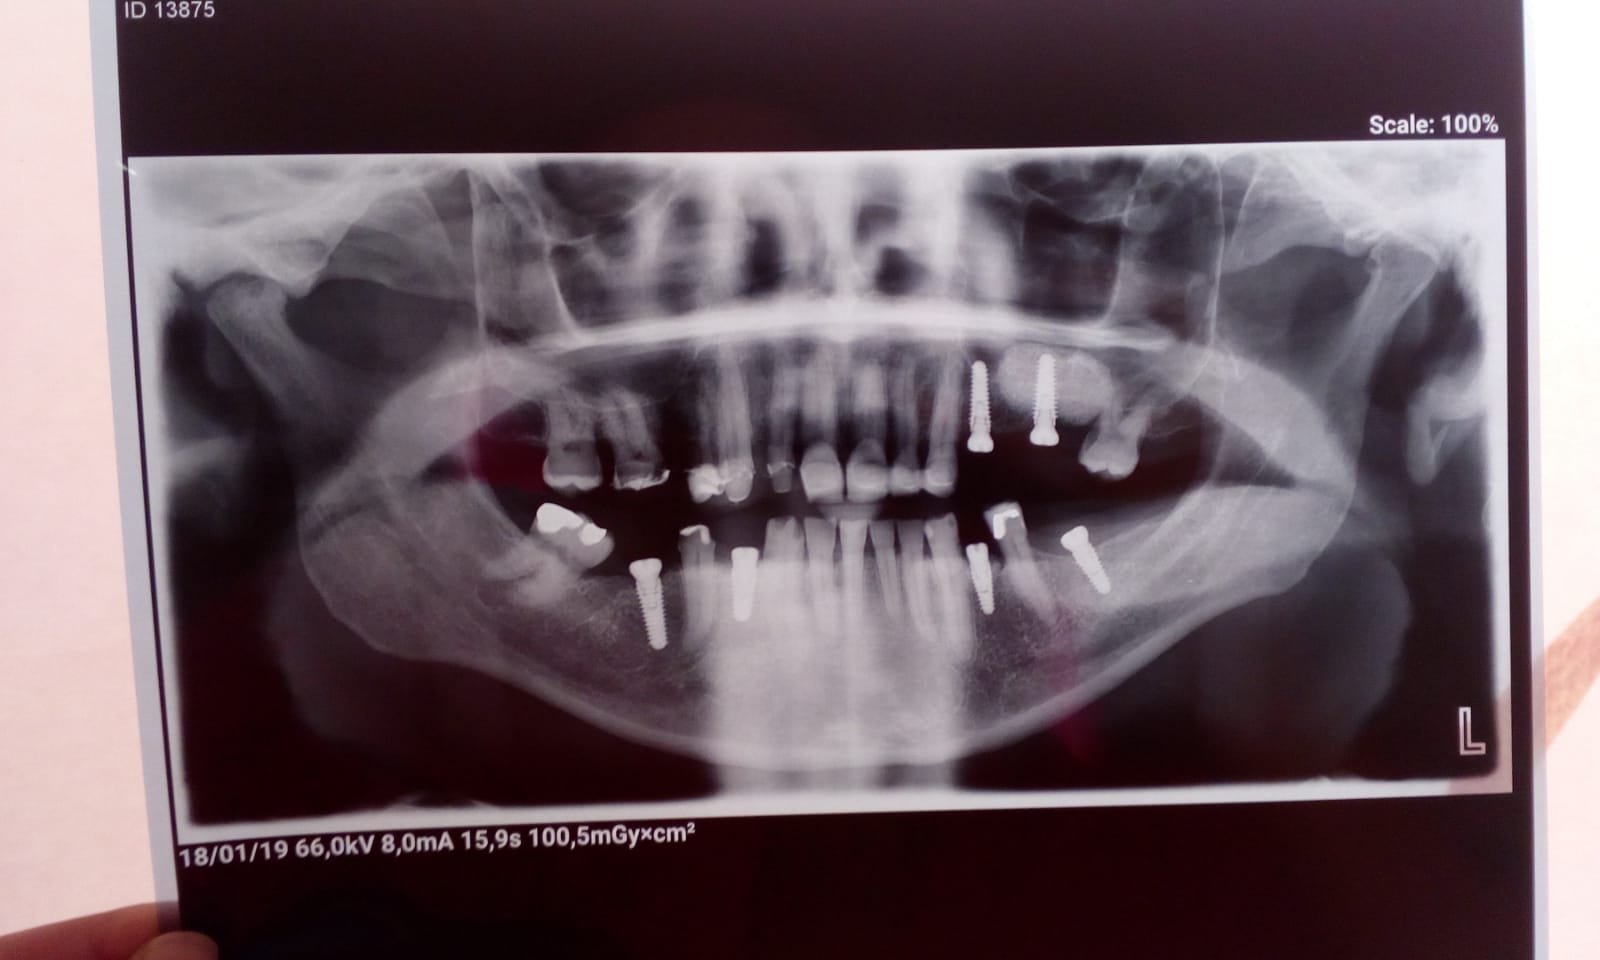

Paciente que acude a nuestra consulta con 8 implantes puestos en Brasil. En el traslado ha perdido la cartilla de id de los implantes y la clinica ha cerrado. Pudo [...]